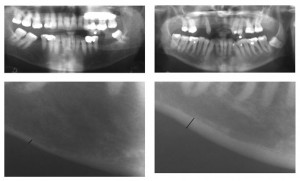

A study now shows that bone worsening in the jaw – which is normally X-rayed before dental treatment – can divulge if bone worsening is occurring in other parts of the body also.

On the back of this study, dentists have developed software called Osteodent that can instantly measure an individual’s threat of osteoporosis, which then warns the patient to whether they need to be referred to a specialist for further investigation.